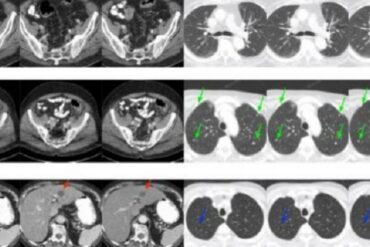

Machine learning has the potential to vastly advance medical imaging, particularly computerized tomography (CT) scanning, by reducing radiation exposure and...